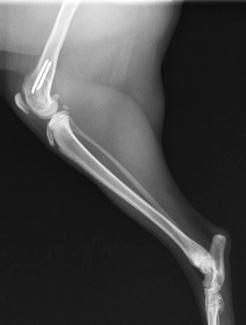

尺骨骨折を伴った肘関節脱臼

手術前レントゲン写真

手術後レントゲン写真

手術中の肘関節の写真